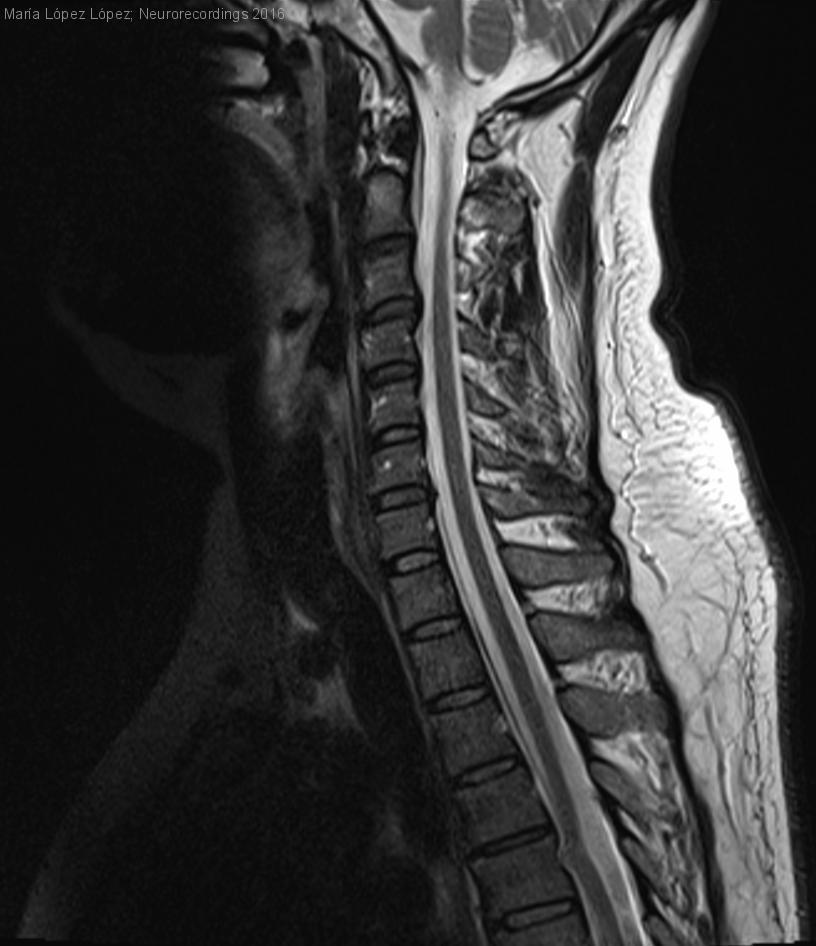

Hombre | 38 años

Diagnóstico final: HERNIACIÓN MEDULAR

Nuestro  paciente había sufrido en el año 2000  un  traumatismo importante con herida penetrante en cavidad torácica izquierda por el ataque de un pez espada,  con resultado de hemoneumotórax y fractura de cuerpo vertebral de D5. Requirió cirugía urgente...